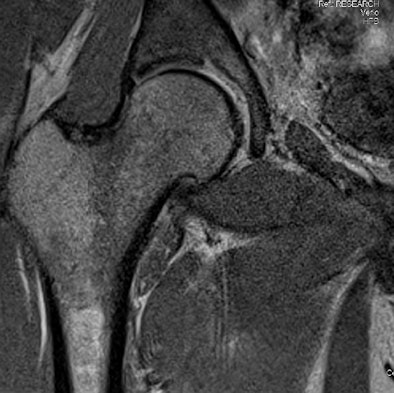

| 3-tesla coronal MR image shows a superolateral acetabular labral tear. Image courtesy of Dr. Bradley Register. |

"The best way we can explain why we found a higher number of labral tears [than previous studies] is that 3-tesla MRI is more sensitive in picking up small tears that may not be visible through arthroscopy," Register said. "With 3-tesla MRI, we are not doing a contrast injection, either. Traditionally, physicians have used arthograms and gadolinium injections in their MRIs to look for labral tears, but recent studies have shown that that is not necessary with 3-tesla MRI."